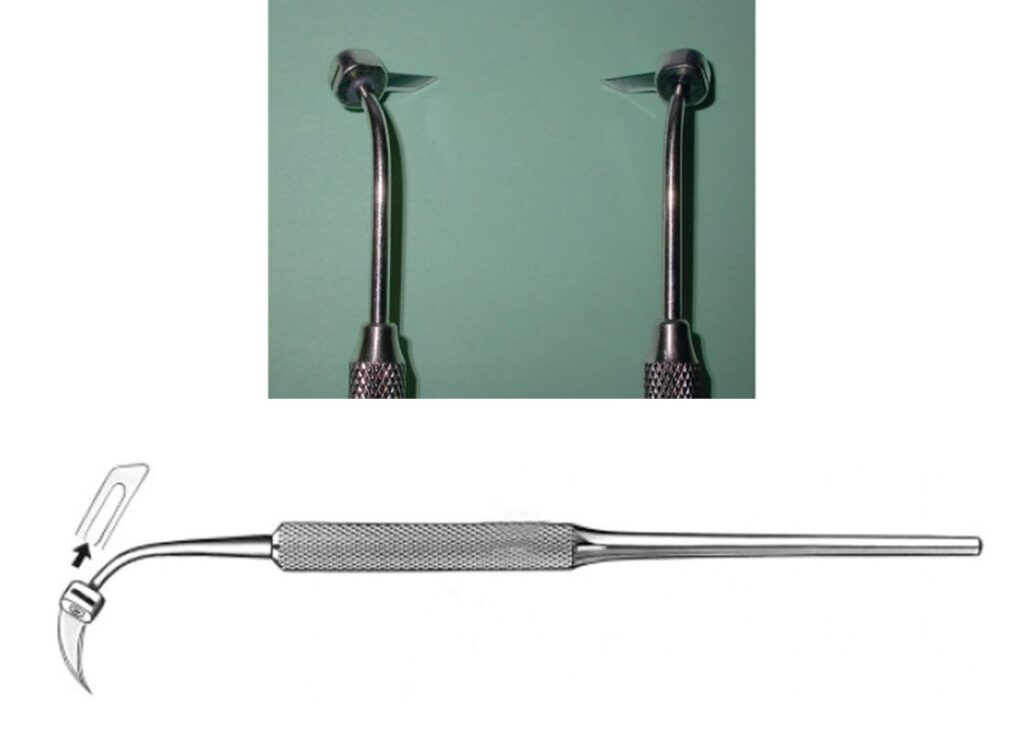

Thiết kế lưỡi số 12 có thể hữu ích cho các đường rạch trong khe nướu (hình 2-11).

Tay cầm khuỷu cũng cho phép cải thiện khả năng tiếp cận các vùng phía sau hoặc trong các thủ thuật cắt nướu (hình 2-12).

Dao Blake (hình 2-13) là một sự bổ sung hữu ích cho phẫu thuật nha chu, đặc biệt là trong các thủ thuật cắt nướu. Lưỡi dao ở một góc nhọn so với tay cầm dụng cụ. Tuy nhiên, những dụng cụ này tương đối khó lắp ráp và làm sạch, đồng thời khiến trợ thủ dễ bị chấn thương do vật sắc nhọn hơn.